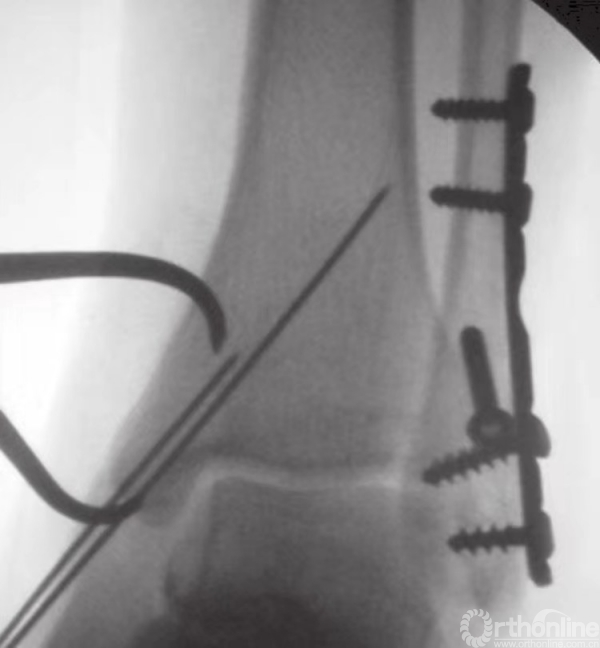

在钳的前方和后方,放置两枚较小的克氏针,并使之与骨折线垂直(图15)。注意要保证克氏针不刺穿踝关节(图16)。为防止刺穿关节,可将角度调至与水平方向约成30°。在克氏针上方和对侧皮质附近,使用管状钻钻孔。后嵌入4mm部分有螺纹的空心松质骨螺钉。

图16 透视下观察克氏针方位及骨折复位情况